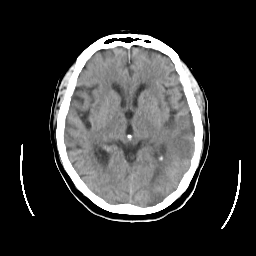

CT Study #2 -- Slice #13